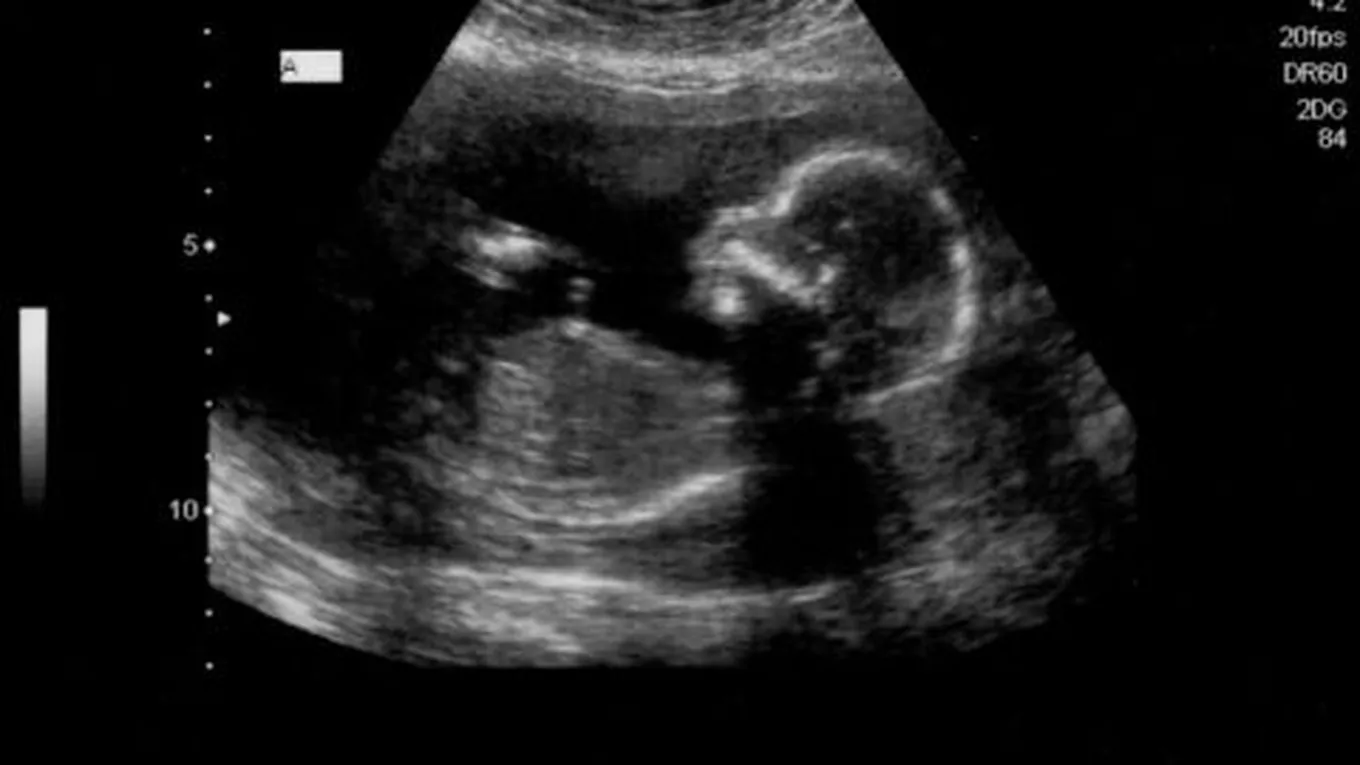

الجنين في الأسبوع السابع عشر

الجنين في الأسبوع السابع عشرعلى الرغم من كل المتاعب التي تمر بها المرأة خلال فترة حملها سواء إن كانت صحية أو نفسية، إلّا أنّها تعتبر أجمل مراحل حياتها ابتداءً

على الرغم من كل المتاعب التي تمر بها المرأة خلال فترة حملها سواء إن كانت صحية أو نفسية، إلّا أنّها تعتبر أجمل مراحل حياتها ابتداءً من اللحظة التي تكتشف فيها بأنّها حامل إلى حين ولادة طفلها ومشاهدته يتنفس بين يديها، والحمل الطبيعي هو الذي تكون مدته تسعة أشهر، ولكبل شهر منها تطورات مختلفة تطرأ على الأم والجنين، فكيف يكون الجنين في الأسبوع السابع عشر من الحمل وما هي التغيرات التي تطرأ عليه وعلى والدته في هذا الأسبوع؟[1]

- يبلغ طول الجنين في هذا الأسبوع ما يقارب 13 سم، أمّا وزنه فيصل إلى 140 غرام تقريباً.

- يبدأ الجنين بسماع الأصوات ولا سيما العالية، والتي بدورها تجعله يحرك يديه ليغطي بها أذنيه عند سماعه لصوت عالي مزعج.

- يبدأ الجنين أيضاً بممارسة حركات طبيعية وهادفة، فعندما تلجأ الأم إلى فحص الدوبلر لتسمع دقات قلبه، فإنّ جنينها يتحرك بعيداً عن مكان وضع الجهاز، لأنه بدوره يصدر صوتاً مزعجاً.

- يصبح أيضاً نشيطاً جداً، فيعمل على تحريك رأسه وذراعيه إضافةً إلى أرجله باستمرار.